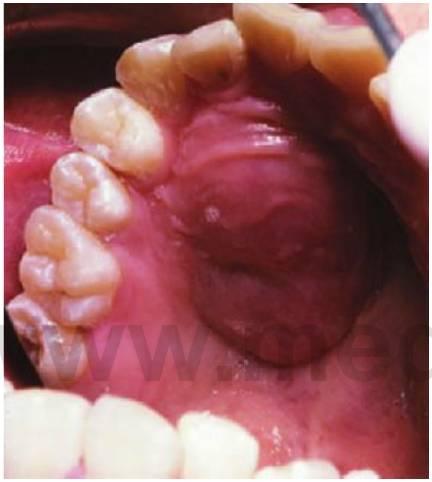

Las complicaciones médicas se evitan con un trasplante renal, que es el tratamiento de elección en niños con insuficiencia renal terminal. A pesar de la limitada disponibilidad de órganos de donantes, el trasplante renal alcanza una elevada tasa de éxito. Las compli caciones asociadas a la inmunosupresión con ciclosporina y prednisona para prevenir el rechazo del órgano deben ser tenidas en cuenta en el tratamiento odontológico. Las manifestaciones orales más habituales después de un trasplante renal son la hiperplasia gingival (fig. 10.10B) y la infección oportunista por flora comensal.